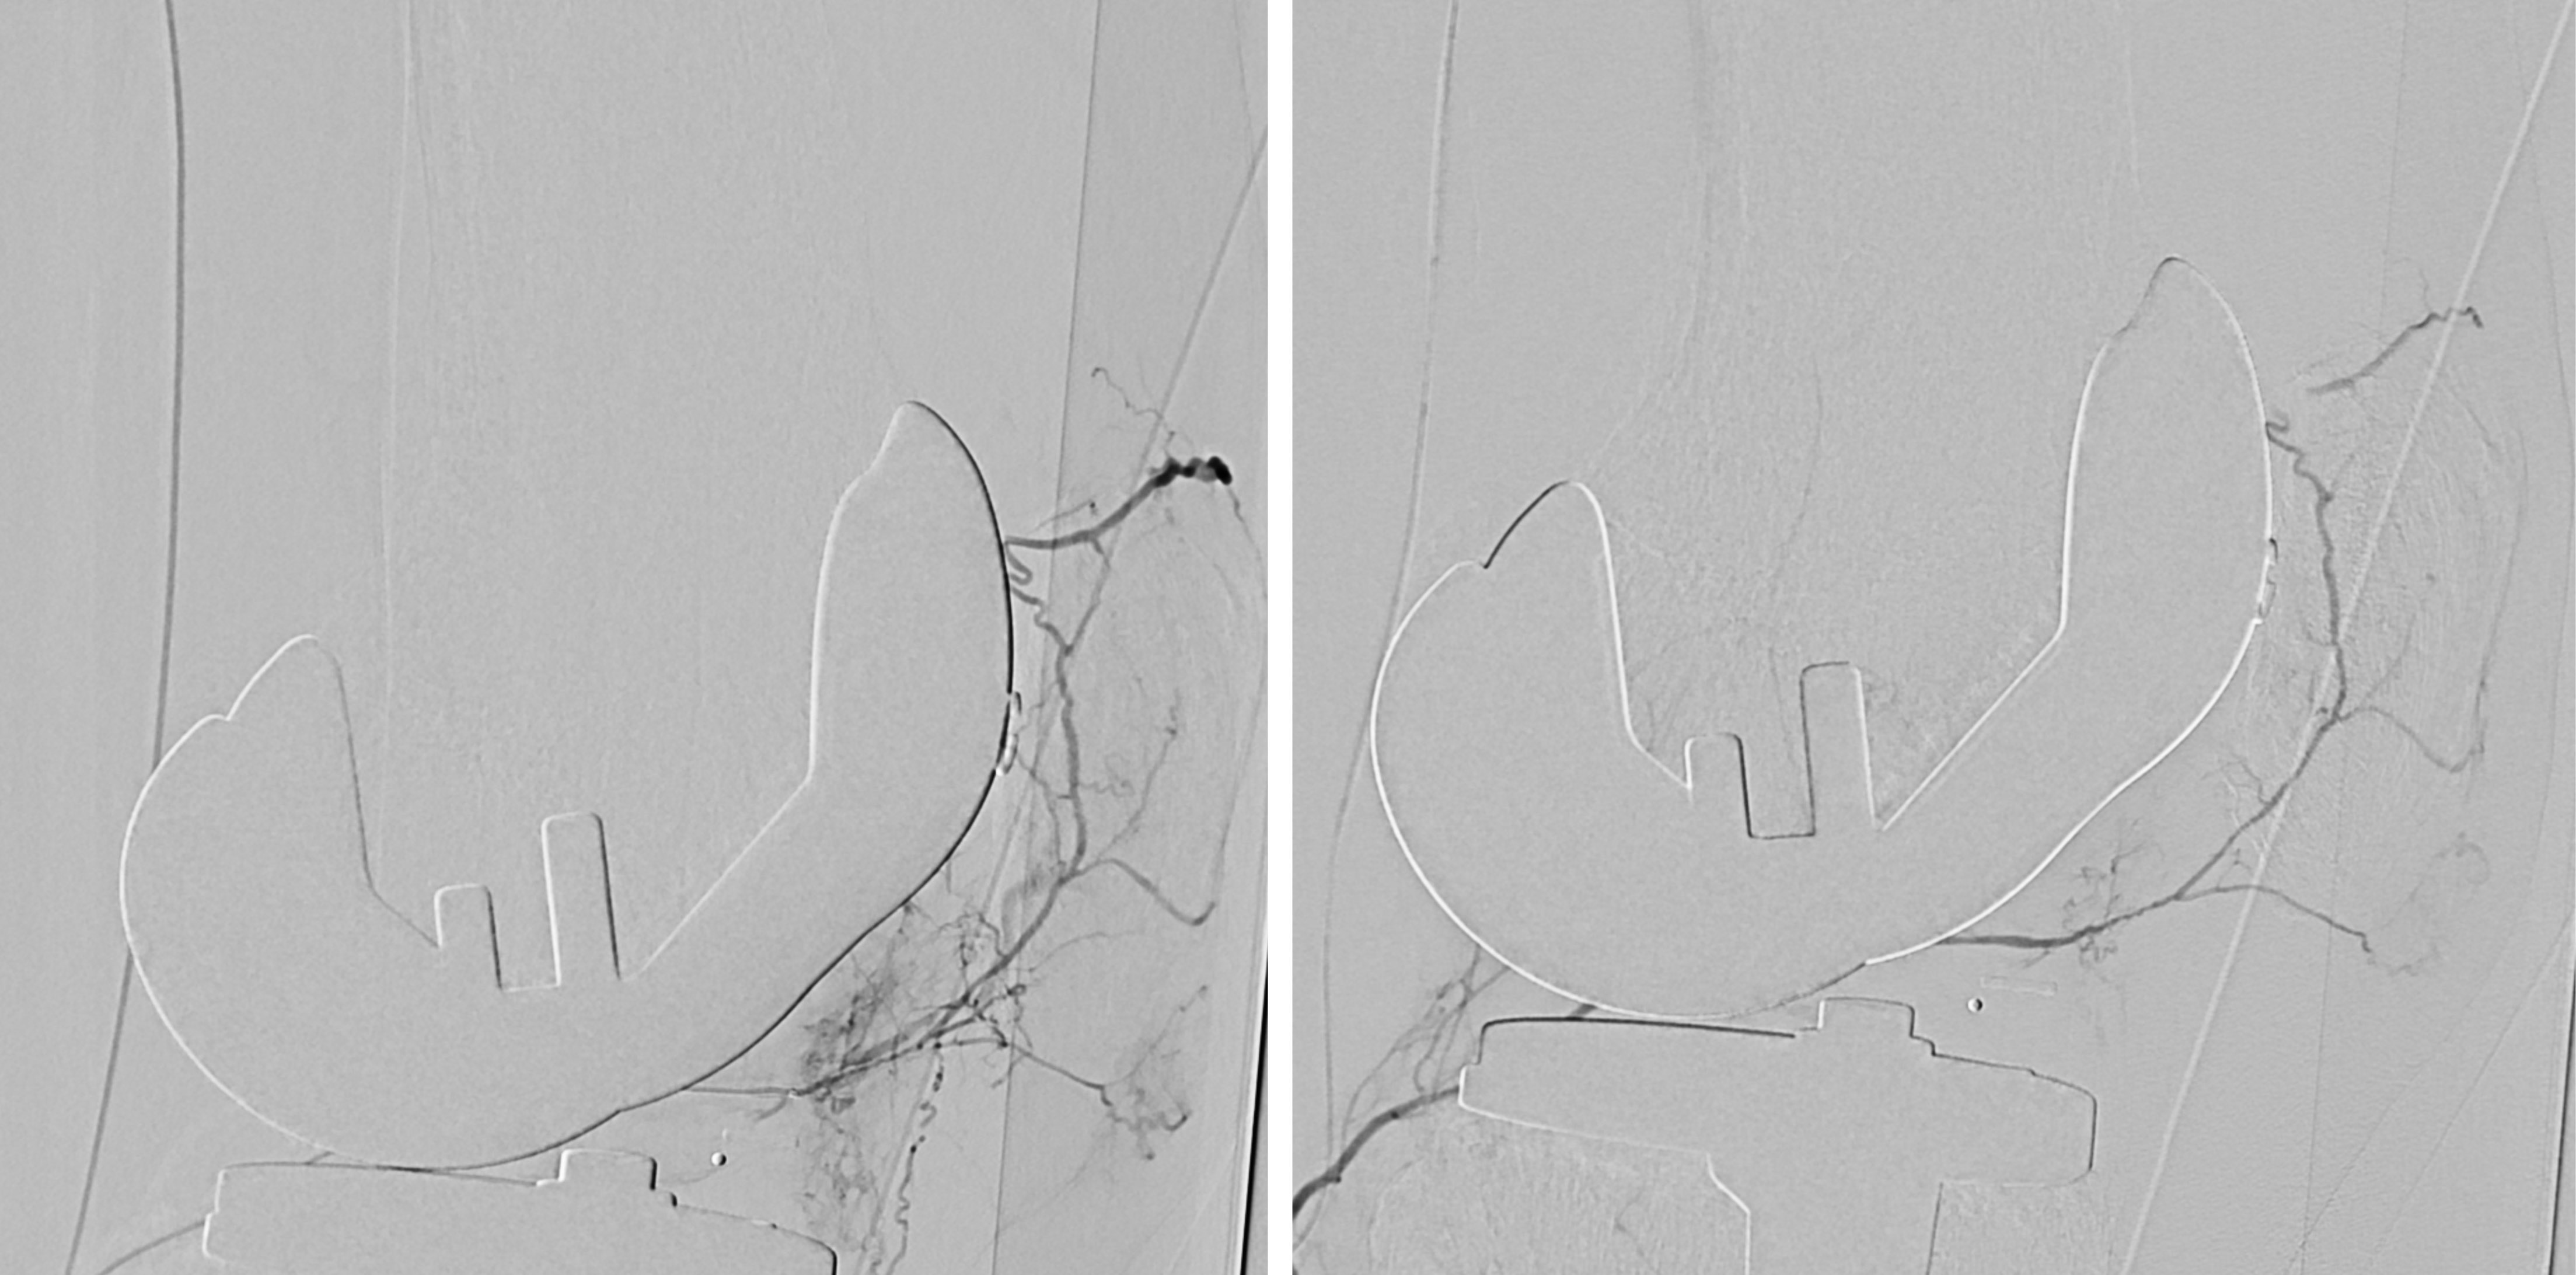

Alternativ zur offenen chirurgischen Therapie eines Aortenaneurysmas besteht die Möglichkeit einer endovaskulären Aneurysmaausschaltung mittels eines Stentgrafts (gewebeummanteltes Metallgittergeflecht). Voraussetzung für die endovaskuläre Therapie ist jedoch eine anatomische Eignung, welche eine ausreichende Weite der Beckengefäße und nötige Verankerungszonen für den Stentgraft mit sich bringt. Die Stentgraft Implantation wird von Interventionellen Radiologen in Zusammenarbeit mit Anästhesist:innen und Gefäßchirurg:innen durchgeführt. Der Eingriff erfolgt unter Spinalanästhesie oder einer Allgemeinnarkose. Der Zugang zum Aneurysma wird üblicherweise durch einen kurzen Schnitt in der Leiste geschaffen. Zur Darstellung des Aneurysmas wird zuerst eine Angiographie der Bauchaorta durchgeführt (Abb.2). Folglich wird unter Röntgendurchleuchtung der Stentgraft über einen Führungsdraht in die Bauchaorta eingebracht und unterhalb der Nierenarterien verankert. Eine Kontrollangiographie nach Stentgraft-Implantation wird zum Nachweis eines guten Ausschlusses des Aneurysmas durchgeführt (Abb.3).

Bei elektiver chirurgischer Sanierung von Descendensaneurysmen wird die 30-Tages-Mortalität mit 5–13% angegeben. Weitere postoperative Komplikationen sind respiratorische Probleme, bis zu 33% neurologische Defizite und renale Insuffizienz bis zu 8%. Die endovaskuläre Stentgraft-Therapie hat deutlich geringere Mortalitäts- und Komplikationsraten und hat als Alternativmethode eine große Bedeutung in der Behandlung von Aneurysmen in der Aorta descendens und des Aortenbogens erlangt. Bei Beteiligung des Aortenbogens sind vorausgehende chirurgische Umbauten von Aortenbogenästen erforderlich, um eine Stentgraft Verankerung zu ermöglichen. Abbildung 4a zeigt ein Aneurysma mit Beteiligung des  Aortenbogens und Abgang der linken Halsschlagader (Arteria carotis) und der linken armversorgenden Arterie (Arteria subclavia) in Nahebeziehung zum Aneurysma. Eine Stentgraft-Therapie kann in solchen Fällen nach Verlagerung (Transposition) der Arteria carotis und Arteria subclavia durchgeführt werden (Abb. 4). Die CT-Kontrolle bestätigt die korrekte Lage des Stent-grafts und den Ausschluss des Aneurysmas.